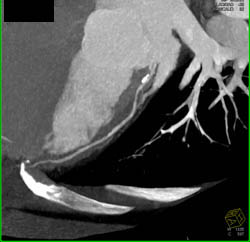

Plaque in LAD